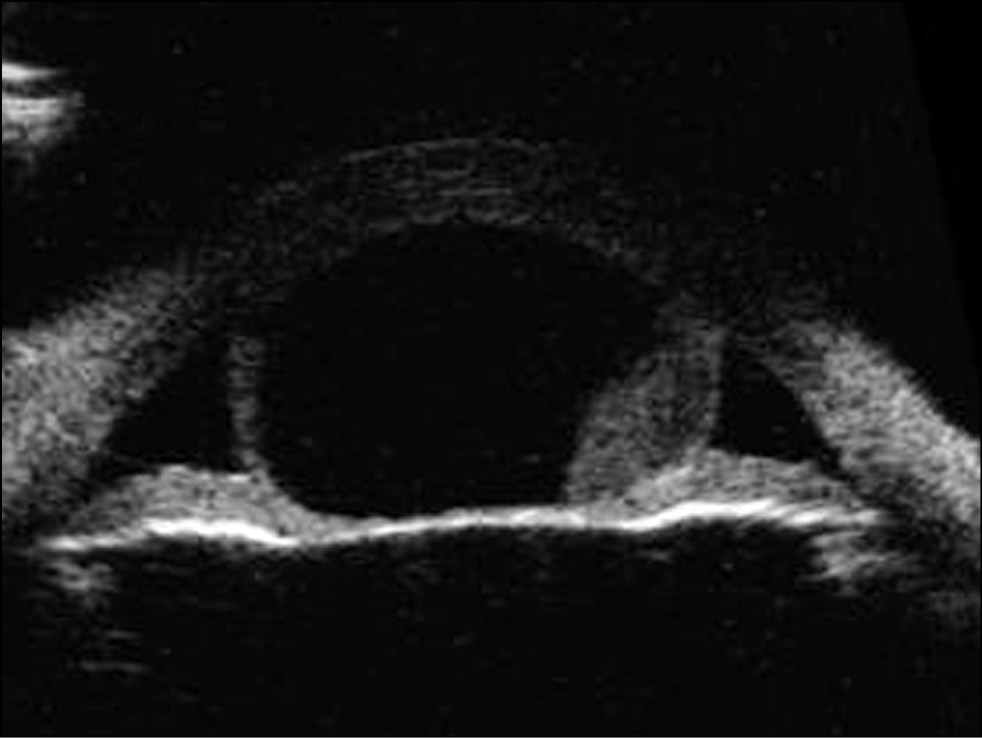

Пациент А., 16 лет. Впервые заметили новообразование радужки у ребёнка в 13 лет, в течение последнего времени отмечают рост. При обращении в Центр острота зрения OU составила 1,0. Проведено обследование, включая ультразвуковую биомикроскопию, при которой выявлены акустические признаки стромальной кисты радужки размером 6,41×2,45×6,62 мм с неоднородным содержимым. УПК в зоне кисты закрыт. При биомикроскопии на радужке в верхневнутреннем квадранте с 12.30 до 15.30 часов, распространяясь от зрачкового края и до цилиарного пояса, определено проминирующее кистозное образование шаровидной формы, с довольно чёткими контурами и гладкой поверхностью, контактирующее с эндотелием роговицы (рис. 9). В полости кисты наблюдали уровень белёсого содержимого, зрачок был немного деформирован и уплощён (рис. 10).

Рис. 9. Стромальная киста радужки.

Рис. 10. Стромальная киста радужки. Ультразвуковая биомикроскопия радужки OD.

По данным оптической когерентной томографии определяется гиперрефлективная поверхность капсулы кисты радужки и гипорефлективный промежуток между эндотелием роговицы и поверхностью капсулы (рис. 11).

Рис. 11. Оптическая когерентная томография радужки OD. Гиперрефлективная поверхность капсулы кисты радужки.

Проведена операция иридэктомия с биопсией правого глаза. Гистологическая картина соответствовала диагнозу стромальной кисты радужки. После операции острота зрения OU составила 1,0. Пациенту рекомендовано динамическое наблюдение.